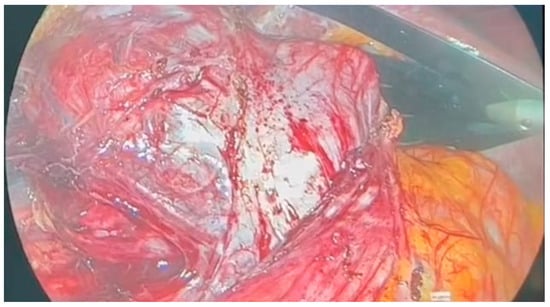

| Our Case Rep | Solid neoplastic proliferation | Spindle cells arranged in a fascicular pattern with areas of coagulative necrosis and areas of hyalinization of the stroma | Frequent mitotic figures | Positivity for SMA, desmin and calponin; negativity for cytokeratin, S100, EMA |